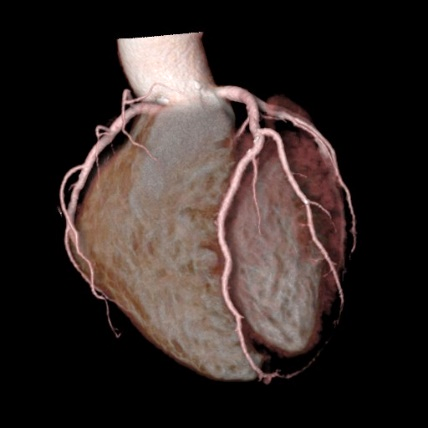

造影剤を用いて撮影すると、臓器や血管の3次元画像を作成することができます。3次元画像では、あらゆる角度から立体的に観察することができ、診断・治療に用いられています。

脳血管 3次元画像

腹部血管 3次元画像